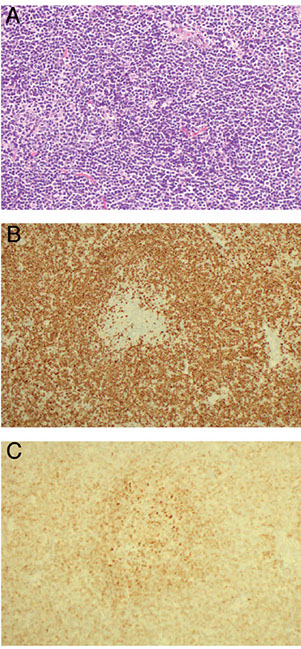

Expression of annexin A1, DBA-44, and BCL1 by hairy cell

leukemia (HCL). This HCL is the same case shown in Figure 4.A through C, The atypical lymphoid cells are positive for annexin A1 (partial) (A), DBA- 44 (B), and BCL1 (partial) (C) (original magnification3400 [A]; original magnification x200 [B]; original magnification x200 [C]).

- these markers

IHC: TRAP is a technically difficult stain to perform

(+) CD20/22/11c/103/25/123, T-bet, annexin-1 (ANXA1), DBA.44, FMC-7, Cyclin D1 (weak), HBME-1, cyclin D1 (weak, and does not harbor the genetic mutation)

(-) CD5 / 10 (+ in 10-20%)/ 23 / 43

- can rarely be CD10+ (need >30%+ cells threshold to call +)

Flow: CD20 bright, CD22 bright, CD103+, CD11c+, CD25+, very few monos in PB/BM

- ANXA1 may be most specific marker (though must be careful bc is expressed by myeloid and T-cells; which is why ANXA1 cannot monitor MRD)

Should have the ABCs of HCL to distinguish from mimickers: Annexin A, BRAF and Cyclin D1